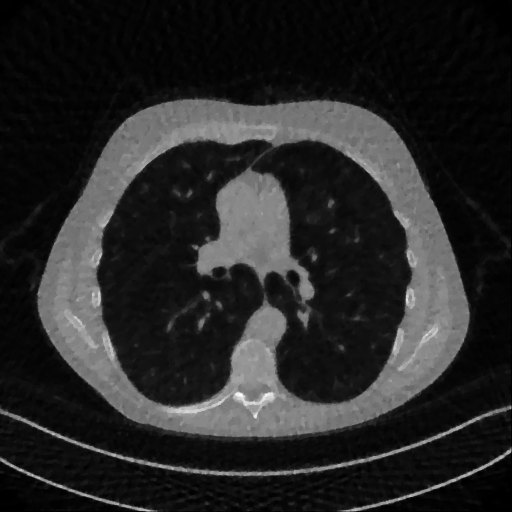

We now consider the P180,60subscript𝑃18060P_{180,60} CT protocol whose results are reported in Figure 6. In this case, the tomographic reconstruction is more challenging than in the previous experiment. The starting image xRISsubscript𝑥𝑅𝐼𝑆x_{RIS} has evident streaking artifacts and blur and some details are lost, especially in the first zoom. The artifacts are reduced in the xISsubscript𝑥𝐼𝑆x_{IS} (top right image), where some details are recovered and the edges are quite neat. The xINGsubscript𝑥𝐼𝑁𝐺x_{ING} image obtained with the proposed RISING (bottom right) is visually an excellent reconstruction. It is very similar to the xLPPsubscript𝑥𝐿𝑃𝑃x_{LPP} image, whose training, we remark, is based on more informative target images.

Figure 6: Results on a test image from the Mayo data set, under the P180,60subscript𝑃18060P_{180,60} CT protocol. Top-left: xRISsubscript𝑥𝑅𝐼𝑆x_{RIS}; top-right: xISsubscript𝑥𝐼𝑆x_{IS}; bottom-left: xLPPsubscript𝑥𝐿𝑃𝑃x_{LPP}; bottom-right: xINGsubscript𝑥𝐼𝑁𝐺x_{ING}.